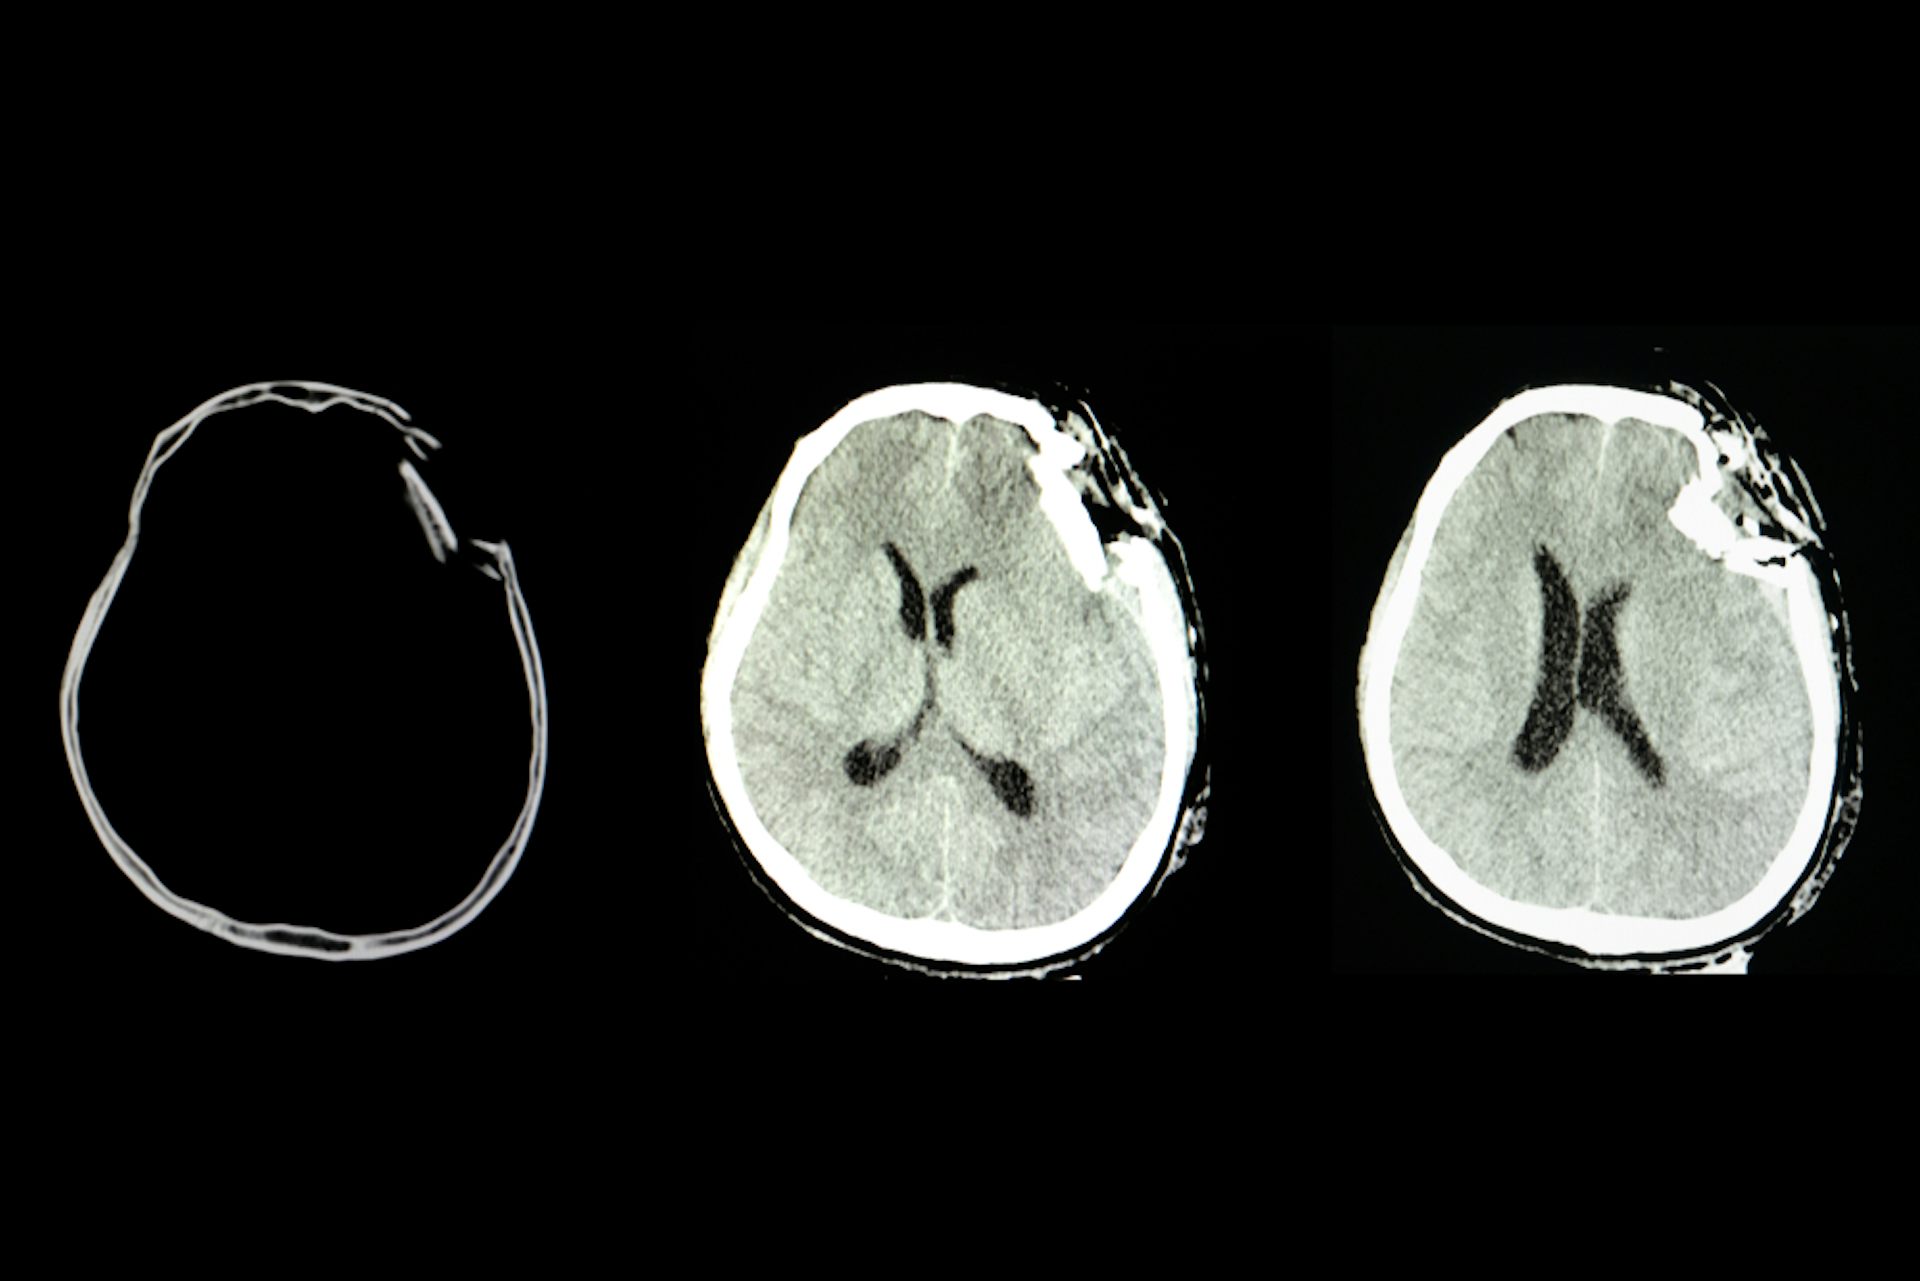

50+ Severe Traumatic Brain Injury Ct Scan Pictures. A severe traumatic brain injury (tbi) affects more than just the injured person. Severe head injury (gcs < 8) + abnormal ct scan.

The effect of a tbi, such as concussion , depends on the severity of the injury and where it occurs. Traumatic brain injury (tbi) is defined as a structural injury to the brain or a disruption in the normal functioning of the brain as a result of a blunt or patients with moderate tbi or severe tbi should be transferred to a neurocritical care unit at the earliest. Tbis can produce microscopic changes that do not appear on ct scans and are several months after a severe head injury, patients with a good score on the gos may have. A severe tbi not only impacts the life of an individual and their family, but it also has a large societal and economic toll.